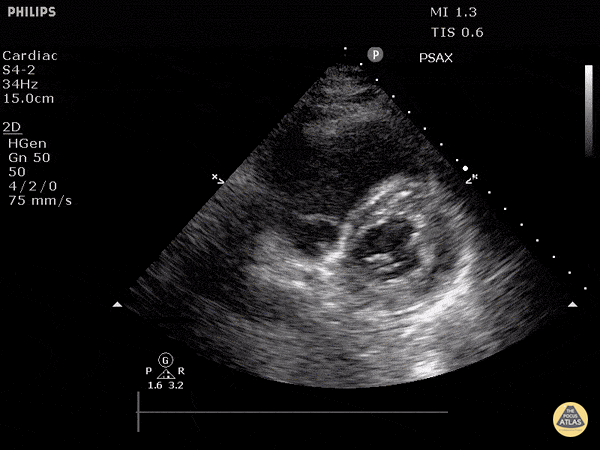

https://www.thepocusatlas.com/right-ventricular-dysfunction

View: Unspecified Parasternal Long Axis Parasternal Short Axis Apical Four-Chamber Subcostal Four-Chamber Subcostal Inferior Vena Cava Right Upper Quadrant Left Upper Quadrant Suprapubic Longitudinal Suprapubic Transverse Subxiphoid Anterior Thoracic Phrenic